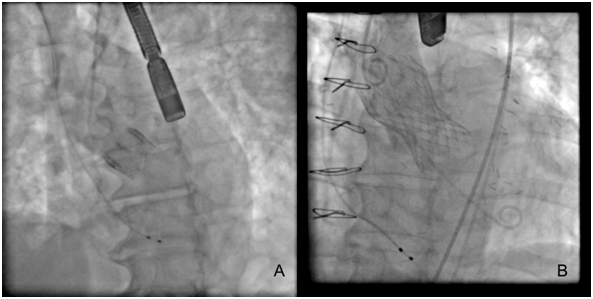

Until this moment, the TAVR devices approved and non-approved are described in (Table 1), and some TAVR devices have their fluoroscopic view demonstrated in (Figure 2). There was a recent report about Lotus valves recall due to pin troubles, following reports of problems with the device’s locking mechanism. The problem, according to the company, is the premature release of a pin connecting the Lotus valve to the device’s delivery system. Boston Scientific expects to reintroduce the Lotus to Europe and other regions in the fourth quarter of this year (2017).20 The most patients considered for TAVR undergo multimodal imaging assessment of the aortic root. The multislice computed tomography and/or three-dimensional echocardiography are the imaging modalities of choice (according to availability and local expertise) to evaluate the annular dimensions (diameters, area, perimeter) and unique anatomical features of each patient. A variety of adverse anatomical features may complicate TAVR procedure, and in such cases the availability of multiple TAVR technologies can facilitate the procedure safety.21